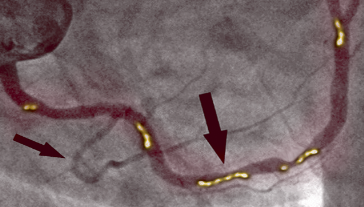

PŘED TERAPIÍ

Na obrázku vlevo vidíme zúžení pravé koronární tepny u 66letého muže, diagnostikované pomocí invazivní koronární angiografie. Je vidět významné zúžení v proximální části způsobené zkalcifikovanou aterosklerotickou plakou, která blokuje průtok krve.